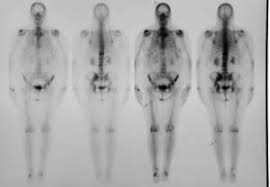

Actually, breast cancer would only cause pain in the ribs as well as tenderness when it has actually spread to the bones, this is a very late stage of cancer and usually, this would not be the first symptom of breast cancer. I was wrongly diagnosed with costochondritis (inflamed cartilage around the ribs) for eighteen months. Limbs (upper arm and upper leg bones) pelvis (hipbones) rib cage. Any type of breast pain can be very distressing, and many women worry they may have breast cancer. Chest wall pain can cause a sharp, stabbing pain. Many people receive effective treatment at this stage and do not develop other. This was followed by left kidney pain which left me shivering, urgency to urinate and extreme thirst and generally feeling unwell. The bones most commonly affected are the: A bone scan (that i eventually insisted on) revealed that i had widespread bone mets. One of the symptoms of lung cancer is rib cage pain or chest pain that gets worse upon breathing deeply, coughing, or laughing. A nagging pain under the right ribcage that won't go away can be a symptom of cancer; Pain in the rib cage can be sharp, dull or achy, and it can be felt at or below the chest or above the naval on either side, explains healthline. Women may feel discomfort and pain as the cancer grows and spreads in the breast.

The tumor in the breast: Unfortunately, breast cancer can recur in the ribs or the chest wall. It is an early stage of breast cancer, meaning the tumor is often very small. Chronic pain experienced in the ribs can be a sign of bone cancer, according to healthline. Limbs (upper arm and upper leg bones) pelvis (hipbones) rib cage. Thickening or lump in breast or other parts of the body: The bone is the most common site of secondary breast cancer. A bone scan (that i eventually insisted on) revealed that i had widespread bone mets. Other symptoms include wheezing, shortness of breath, and coughing up phlegm or blood. With this type of cancer, the area of skin over the tumor can. Back pain can be a symptom of metastatic breast cancer because when this disease spreads, it often goes to bone, benjamin smith, m.d., an associate professor of radiation oncology at md anderson. Do not take a diagnosis of muscle pull as the gospel if that tiny voice inside of you isn't quite agreeing with this. Pain in the rib cage can be sharp, dull or achy, and it can be felt at or below the chest or above the naval on either side, explains healthline.

Breast Cancer Overview Cancer Council Victoria from www.cancervic.org.au Metastatic breast cancer can involve back pain. Other symptoms include wheezing, shortness of breath, and coughing up phlegm or blood. Before this symptom actually occurs, a patient would invariably experience a lump in the breast or changes in the skin of. Secondary breast cancer in the bone is not the same as having cancer that starts in the bone. This pain worsens from coughing, deep breathing, or even laughing. With this type of cancer, the area of skin over the tumor can. Women may feel discomfort and pain as the cancer grows and spreads in the breast. A doctor should be consulted to properly diagnose the condition with a bone scan.

Upper bones of the arms and legs. A sudden, noticeable new pain is the most common symptom of cancer that has spread to the bone. Unfortunately, it can often be a sign of certain cancers, too. Do not take a diagnosis of muscle pull as the gospel if that tiny voice inside of you isn't quite agreeing with this. The tumor in the breast: Cancer cells that spread to the bone often affect these places: Research shows that pain under the right breast is not an indicator of breast cancer, but, in rare cases, it may be a sign of a cancer that has spread to the lungs. Metastatic, or stage 4, breast cancer is terminal, but many people live for decades after a diagnosis. In adults, metastatic bone cancer is much more common than primary bone cancer. Thickening or lump in breast or other parts of the body: Many people receive effective treatment at this stage and do not develop other. This pain worsens from coughing, deep breathing, or even laughing. Secondary breast cancer in the bone is not the same as having cancer that starts in the bone.